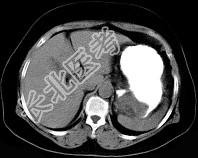

- 单项选择题女43岁上腹不适多年,体检行CT扫描如图, 最可能的诊断为 ( )

A、胃癌

B、胃平滑肌瘤

C、胃平滑肌肉瘤

D、胃淋巴瘤

E、胃蛔虫团块

- 女43岁上腹不适多年,体检行CT扫描如图